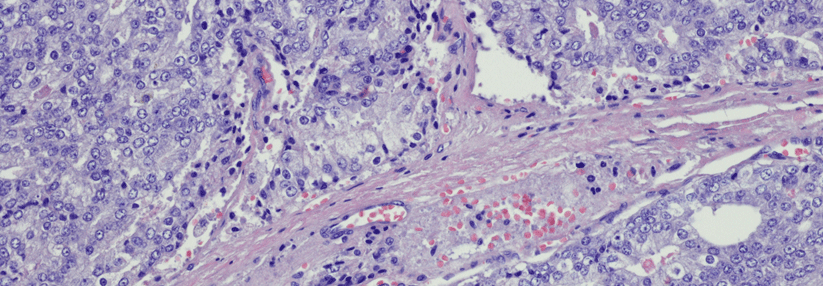

Bei geschlechtsangleichenden Mann-zu-Frau-Operationen wird die Prostata üblicherweise belassen. Transsexuelle Frauen brauchen also auch eine Krebsvorsorge für die Prostata.